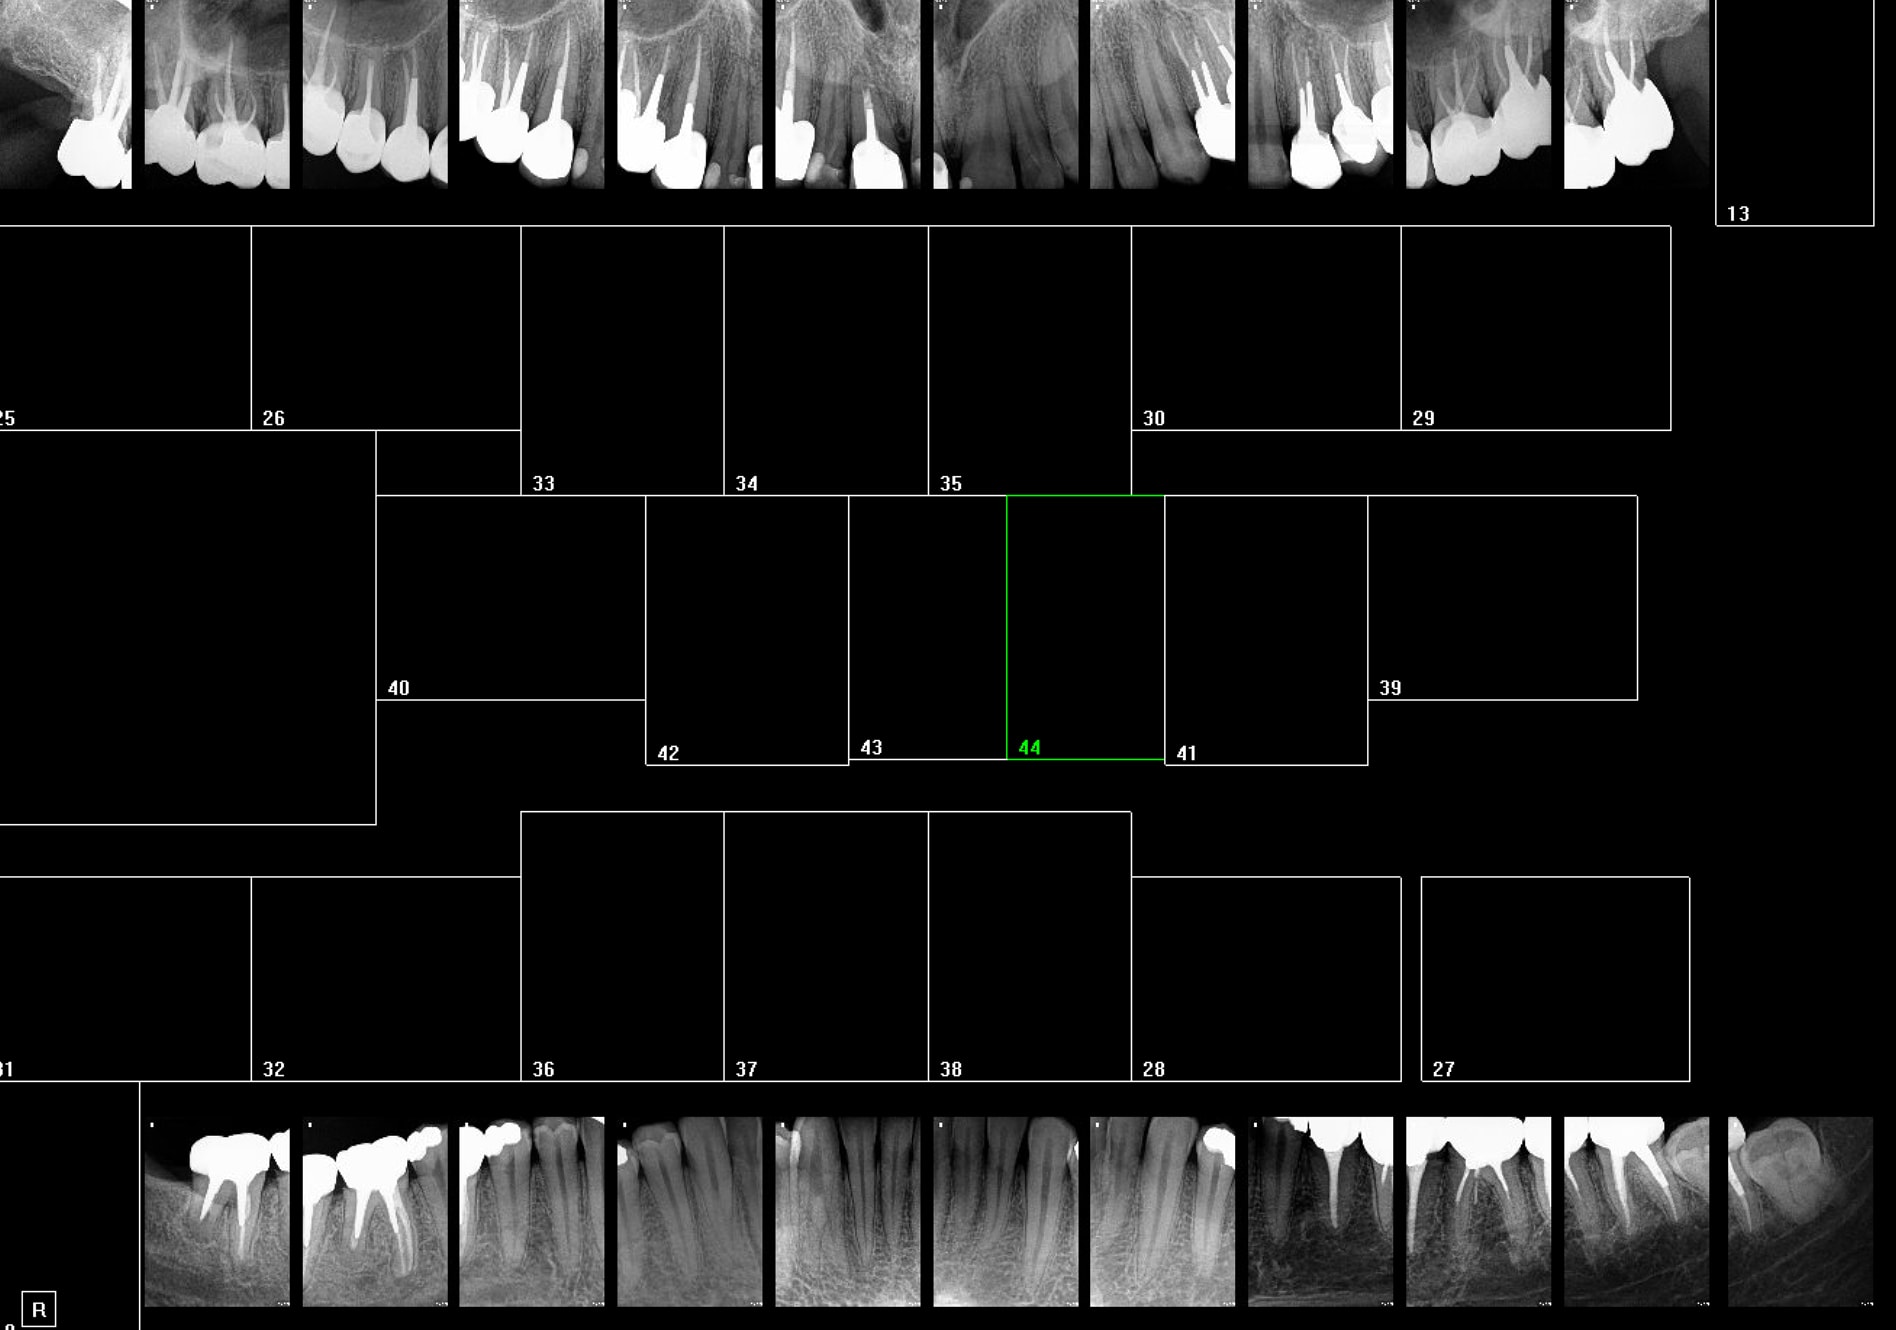

Non. ca c'est pour le bilan tib complet. Genre ça.

T'inquiètes celle ci a très bien compris pourquoi sa 22 la fait souffrir. Rétro coronaires + rétro alvéolaires si justifiées. Point.

Voici la liste des patients dont vous avez à justifier les panos. Indication, compte rendu et orientation thérapeutique s'il vous plait.